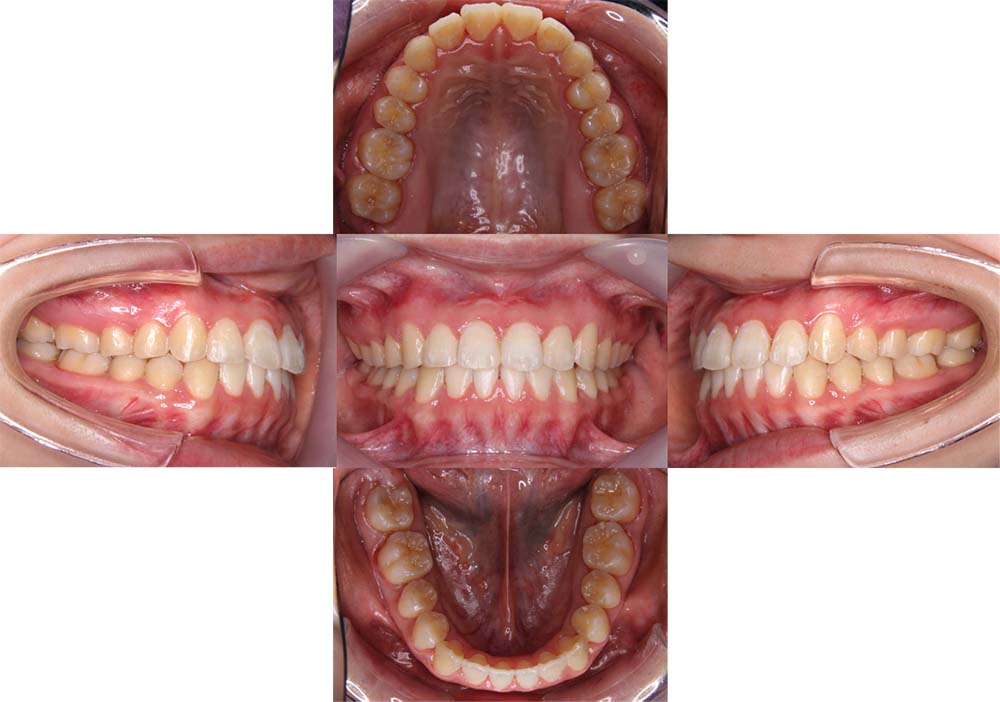

症例02

| 主訴 | 下あご顎が出ている。曲がっている。 |

| 診断名あるいは主な症状 | 反対咬合、非対称、空隙歯列、過蓋咬合 |

| 年齢/性別 | 19歳・女性 |

| 矯正ステージ | 大人の矯正治療 |

| 治療方法 | ワイヤー矯正、顎矯正手術の施行 |

| 抜歯部位/抜歯有無 | 非抜歯 |

| 治療内容 | 上下顎歯列を並べた後に顎矯正手術の施行。 |

| 費用 | 保険治療 |

| 治療期間 | 3年2ヶ月 |

| 主なリスク・副作用 | 痛み、歯根吸収、歯肉退縮、虫歯、後戻り |